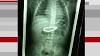

ER visits almost double for young children swallowing objects Before children explore the world on foot, they explore it with their five senses. Early development often includes children listening, looking, touching, smelling and tasting their way through their surroundings. The mouth is one of the first body parts that babies ...

Kids' ER Visits for Swallowing Toys, Foreign Objects Have Doubled Since 1990s By Alan Mozes HealthDay Reporter. (HealthDay). FRIDAY, April 12, 2019 (HealthDay News) -- About 100 kids a day are rushed to U.S. emergency rooms after accidentally swallowing a toy piece, battery, magnet or other foreign object, according to new ...

Young kids going to the ER in droves over swallowed toys, coins and batteries CHICAGO — The number of young kids who went to U.S. emergency rooms because they swallowed toys, coins, batteries and other objects has nearly doubled, a new study says. In 2015, there were nearly 43,000 such visits among kids under 6, compared ...